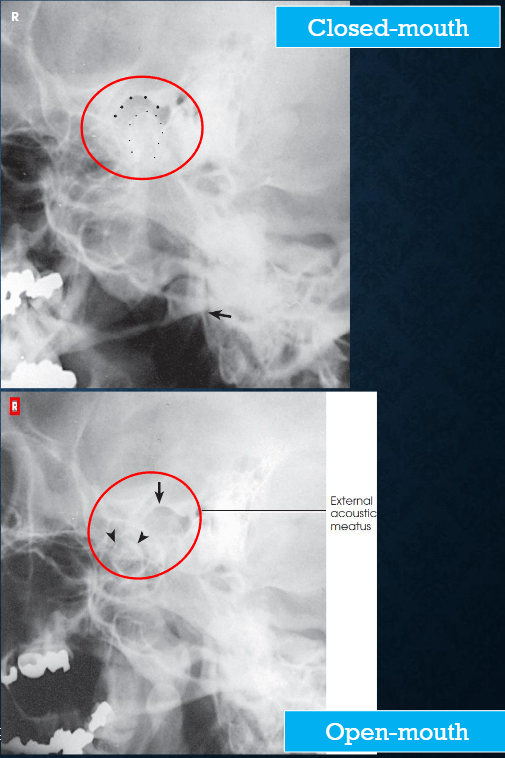

Axiolateral (modified Schuller) TMJs

patient position:

right or left lateral, both sides done for comparison

semiprone or upright

part position:

center ½ inch anterior to the EAM to the IR

head in true lateral

MSP parallel with IR

IPL perpendicular

one exposure with the mouth closed, and a second with the mouth open (if not contraindicated

respiration suspended

CR:

25-30 caudad

enters ½ inch anterior and 2 inches superior to upside EAM

collimation:

1 inch betond the anterior skin line, posteior and inferior to the TMJs

Axiolateral (modified Schuller) TMJs image criteria

TMJ with mouth open and closed

both sides done for comparison

TMJ anterior to EAM

closed mouth: condyle in mandibular fossa

open mouth: condule inferior to the articular tubercle